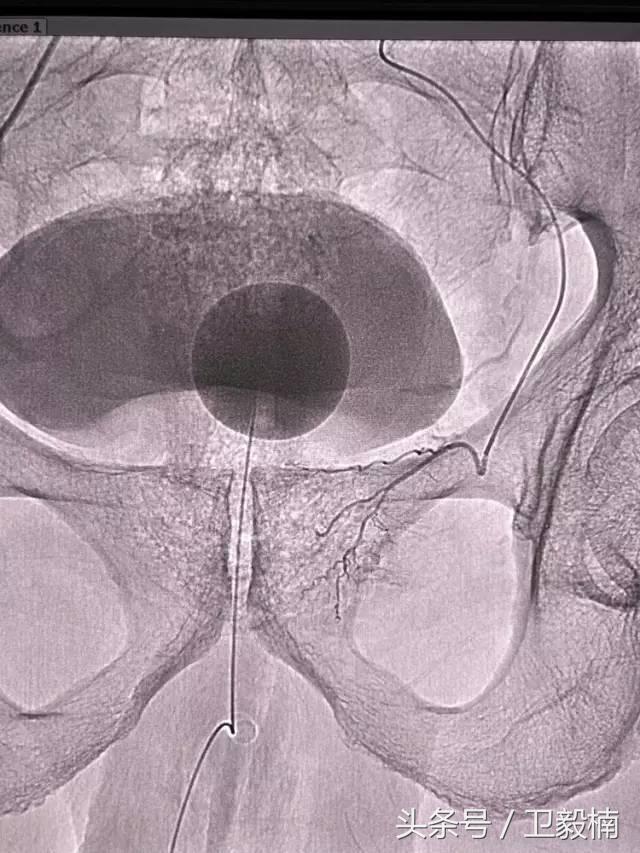

五、出血性疾病:鼻腔大出血、咯血、上消化道大出血、经皮肾镜术后出血、膀胱出血、产后出血等

2、经导管血管栓塞法(Transcatheter embolization)

经原血管造影的导管或特制的导管,将栓塞物送至靶血管内,一是治疗内出血如外伤性脏器出血、溃疡病、肿瘤或原因未明的脏器出血。另一是用栓塞法治疗肿瘤,因肿瘤循环部分或全部被栓塞物阻断,以达控制肿瘤之生长,或作为手术切除的一种治疗手段;亦可用于非手术脏器切除,例如注射栓塞物质于脾动脉分支内,即部分性脾栓塞,以治疗脾功亢进,同时不影响脾脏的免疫功能。

60年*开代**始应用于动脉,使狭窄的血管扩张,70年代研制双腔气囊导管成功后,得到广泛应用,多用于髂、股、腘动脉及肾动脉。肾动脉PTA(或PTPA)多用于肾源性高血压,使狭窄肾动脉扩张,从而降低血压。PTA亦可用于冠状动脉,称为经皮腔内冠状动脉成形术(Percutaneous transluminal coronary angioplasty,PTCA),使硬化的冠状动扩张,以达到治疗冠心病的目的。PTA使用的导管为带胶囊的双腔导管,将胶囊段置于狭窄血管处,囊内注入含有造影剂的液体,加压至3~6个大气压,每次持续10—15o。加压可重复3~4次,多数能使狭窄血管达到扩张的效果。

PTA多用于动脉粥样硬化性狭窄的血管,其机理是粥样斑块受压,内膜和中层撕裂、伸展,使管腔增宽。其他原因的血管狭窄,如多发性大动脉炎,先天性血管狭窄,有时也可用PTA治疗。